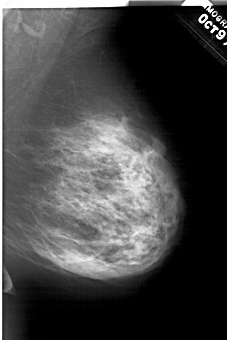

A_1469_1.RIGHT_MLO

RIGHT_MLO LINES 6106 PIXELS_PER_LINE 4081 BITS_PER_PIXEL 12 RESOLUTION 43.5 NON_OVERLAY